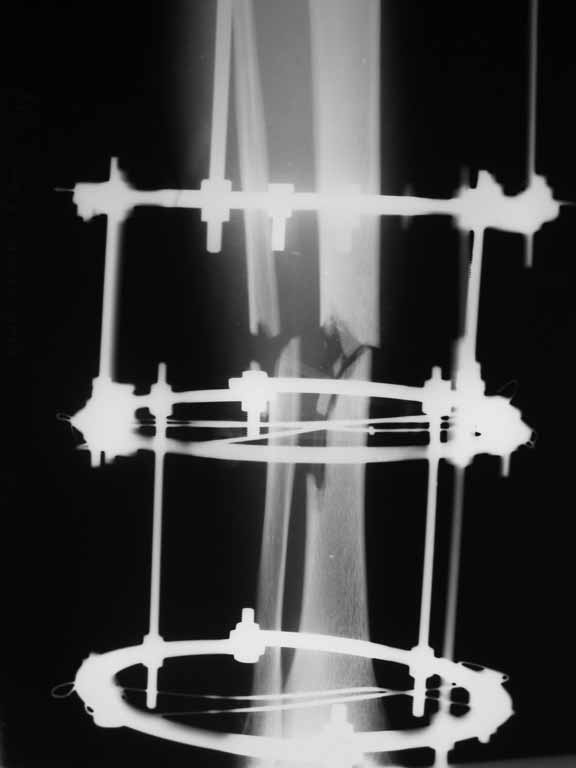

[Ortho] Перелом большеберцовой кости с дефектом дифизарной части

Извините, не загрузились сразу все рентгенограммы.